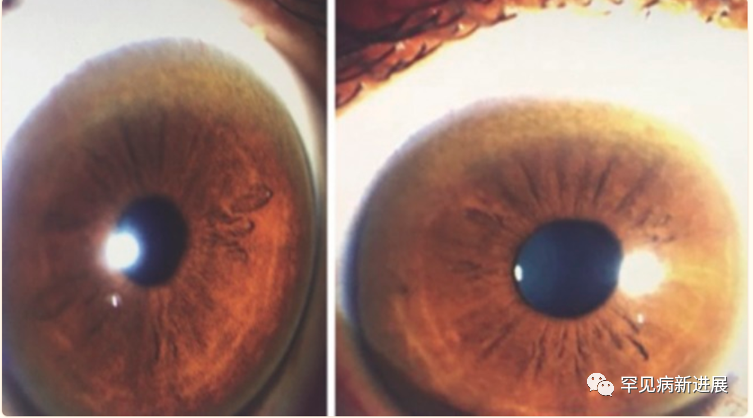

病例情况 病例一:伴有帕金森症状的共济失调型;病例二:伴有帕金森症状的肌张力障碍。两名患者均接受裂隙灯检查有 K-F 环(图1)。 肝脏超声检查有明显结构异常,实验室检查肝功能正常,低血清铜、低铜蓝蛋白和尿铜排泄增加,均无基因检测。(表一) 据统计50% 的肝脏和 99% 的神经系统病变患者有K-F 环(后弹力膜上铜沉积)。 表2: 第8届WD国际会议诊断标准(Leipzig评分) 注:总分≥4分可确诊;总分3分为疑似诊断,需进一步检查;总分≤2分基本不考虑诊断;a:肝铜定量不可及时;ULN:正常值上限 脑部磁共振成像未显示典型的双熊猫征,但在壳核、尾状核和丘脑核上显示对称的 T2/FLAIR 高信号(图 2和图 3)。 两案例均高度暗示了矿物沉积,根据 Leipzig评分,均是 WD 的明确案例。 案例 1 的T2加权序列的代表性图像。背侧区域有高信号B.上中脑轴向切开;中脑被盖上有汇合的高信号C.外侧裂轴向切开;外侧丘脑、尾状核和壳核区有明显的高信号D.岛状区轴向切开;在丘脑和基底神经节可见广泛的双侧高信号E. Corona radiata 轴向切割;双侧半卵圆形未出现任何信号异常 案例 2 的T2加权序列的代表性图像。脑桥背侧区域有高信号B.上中脑轴向切开;黑质C区有外观正常的红色核高信号。壳核上有明显的高信号,有磁化率伪影区域,左侧多于右侧D.侧脑室区域轴向切割,壳核和尾状核上可见连续广泛的高信号E.冠状放射状轴向切割,双侧半卵圆形未见任何信号异常。 由于这种疾病的罕见性,启动基于人群的筛查并不具有成本效益。但对于无法解释的神经系统疾病伴或不伴相关肝病的患者,筛查应该强制性。WD 须与诸如特发性震颤、年轻发病的帕金森病、全身性肌张力障碍和其他罕见的运动障碍(如亨廷顿病、Hallervorden-Spatz 病、特发性扭转性肌张力障碍、舞蹈病-棘红细胞增多症和良性家族性舞蹈病)区分开来。因此,WD 是一种诊断紧急情况,需要立即全面检查。 管理 至于治疗,明确的治疗包括肝移植,特别是对于急性肝炎或暴发性肝功能衰竭的患者。对严重和神经系统后遗症患者,最好的选择是直接增加尿中铜的排泄,即 D-青霉胺和曲恩汀,或阻断胃肠道对铜的吸收,即锌剂和四硫代钼酸盐(表三)。低铜饮食是主要的治疗方法,并补充锌,随后注意到言语、震颤和四肢僵硬的显著改善。第一个病例接受了 D-青霉胺治疗,药物输注缓慢以减少血液不良后果并监测反常的神经功能恶化。至于第二个病例,由于基线神经系统状态相对严重且恶化风险高,该患者继续服用锌补充剂。因无两个相同 WD 患者,治疗应个体化。对螯合剂和药物治疗无效的衰弱性运动障碍患者,可提供肉毒杆菌毒素注射。筛查患者的兄弟姐妹并监测他们的血清铜蓝蛋白也是管理的重要组成部分。早期干预有更好预后,治疗应紧迫。 表三